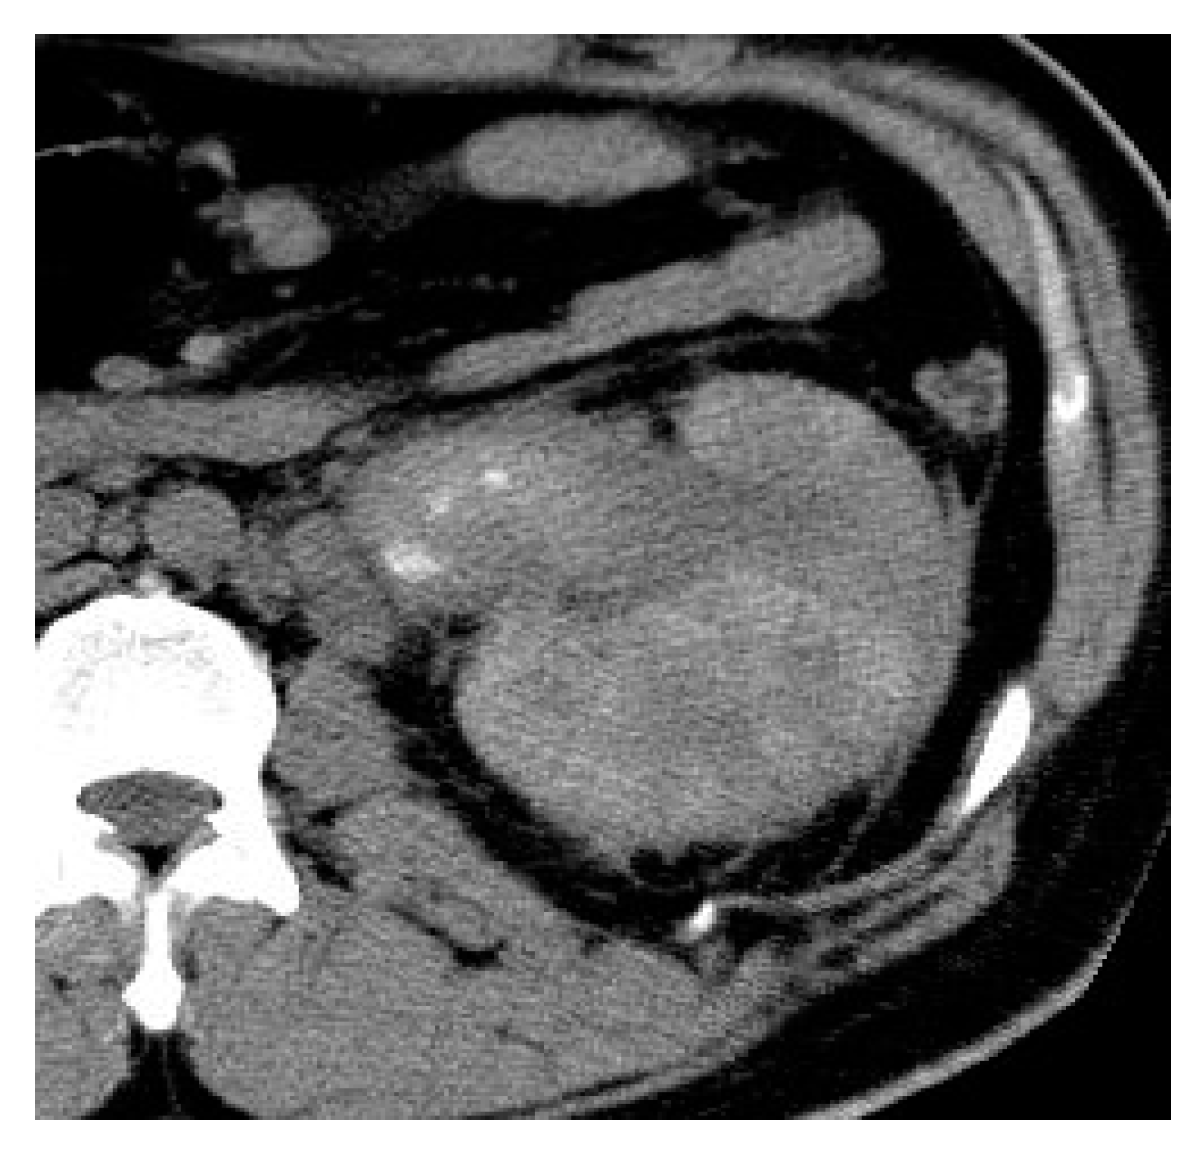

2.2. Renal and Perinephric Abscesses

| Renal abscesses | Round or geographic non-enhancing central fluid collection and enhancing rim. Perinephric fat stranding and thickening of Gerota’s fascia. |